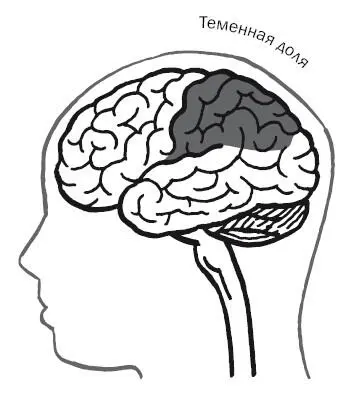

Такие случаи, как у Вильсона и Дугласа, возникающие в результате повреждения теменной доли, печально знакомы неврологам. Вильсон имел «синдром игнорирования» одного полушария – неспособность замечать половину окружающего мира.